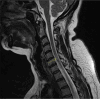

Figure II

Magnetic resonance imaging scan of the spinal cord in T2-weighted image, sagittal plane. Multiple sclerosis lesions in the spinal cord (hyperintense areas)